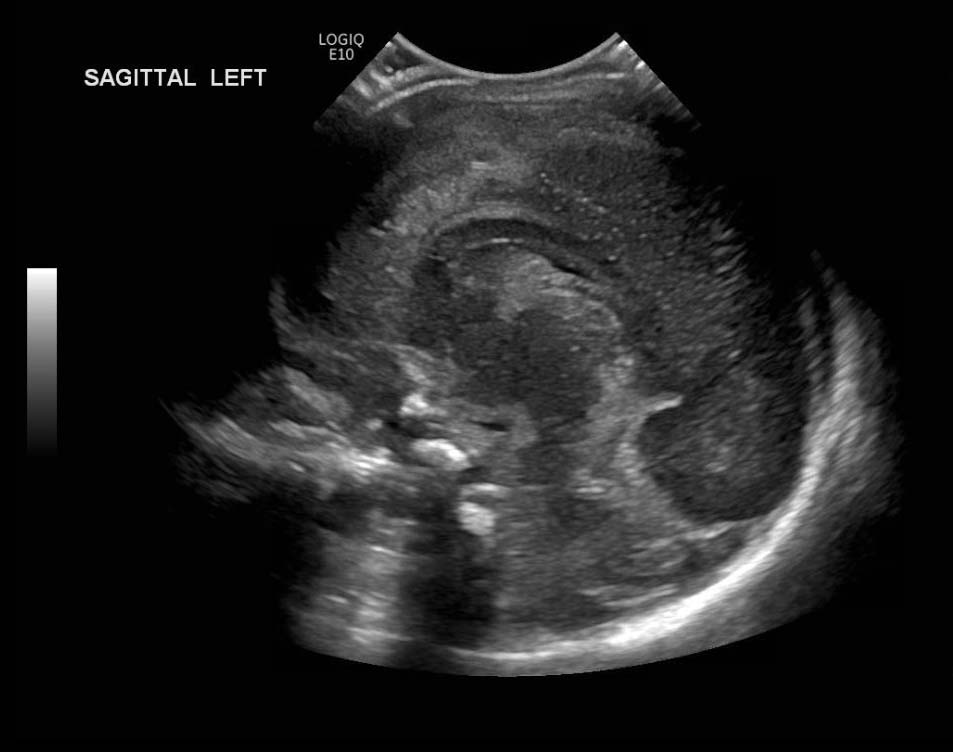

Age: 4 days (born at 24 weeks)

Sex: Male

Indication: Evaluate for germinal matrix hemorrhage

Grade 2 germinal matrix hemorrhage

Sample ReportLeft germinal matrix hemorrhage involving the caudothalamic groove and layering in the occipital horn of the left lateral ventricle without hydrocephalus (grade 2).

No abnormal brain parenchymal echogenicity or extra-axial collections.

Premature sulcation pattern.